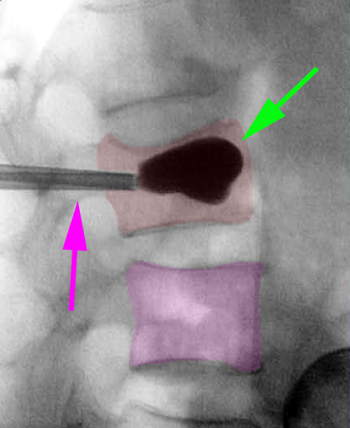

Διαδερμική κυφοπλαστική, ακτινοσκόπηση. Η ειδική βελόνη εισέρχεται διαδερμικά στο σώμα του σπονδύλου (φούξια βέλος) και γίνεται έκπτυξη μπαλονιού το οποίο ανατάσει το οστεοπορωτικό κάταγμα (αριστερά). Κατόπιν πραγματοποιείται έγχυση ακρυλικού πολυμερούς στο σώμα του σπονδύλου για να σταθεροποιηθεί το αναταχθέν κάταγμα (δεξιά). |